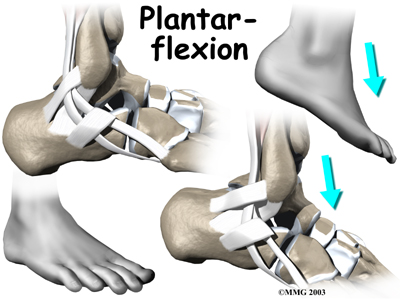

The tendons of these two muscles pass together in a groove behind the lateral malleolus. (Tendons attach muscles to bones.) The tendons are kept within the groove by a sheath that forms a tunnel around the tendons. The surface of the tunnel is reinforced by a band of tissue called a retinaculum. Contracting the peroneal muscles makes the tendons glide in the groove like a pulley. The pulley action causes the foot to point (plantarflexion) and (eversion).